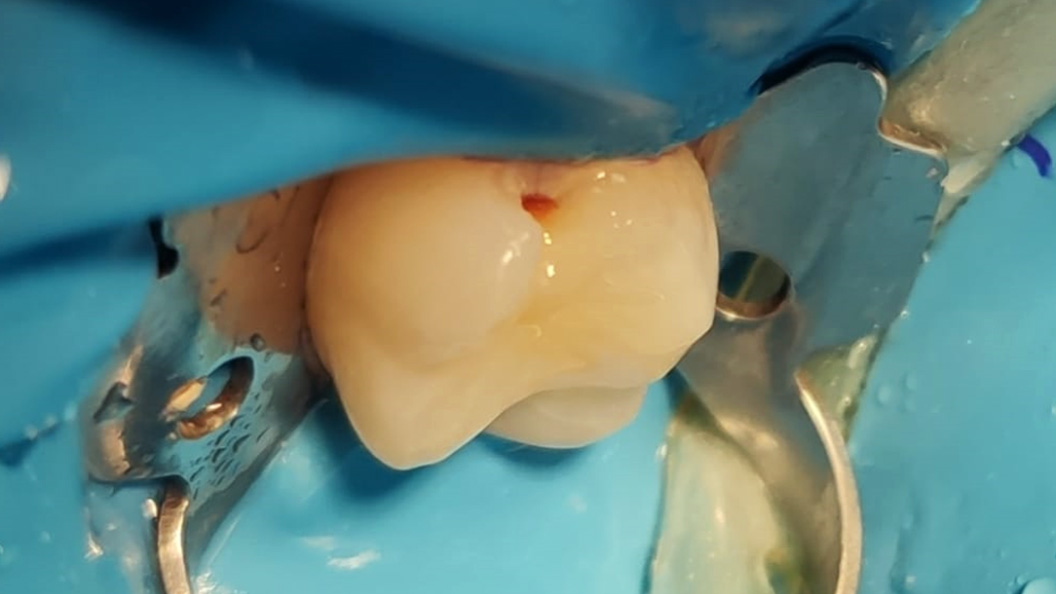

Пациент обратился с жалобами на эстетический недостаток в верхнем жевательном зубе справа, который был выявлен в ходе подготовки соседних зубов под коронки. После обработки кариозной полости под контролем кариес-маркера, был выявлен кариес средней глубины, дно и стенки полости плотные. Реакция на холодовую пробу и перкуссию отрицательна. Поставлен диагноз: хронический средний кариес.

В ходе лечения были проведены следующие работы:

- с использованием системы OptaGate механическая обработка кариозной полости

- медикаментозная обработка с использованием хлоргексидина 2%

- поставлена пломба Fuji II

- проведено микроконтурирование и макроконтурирование пломбы